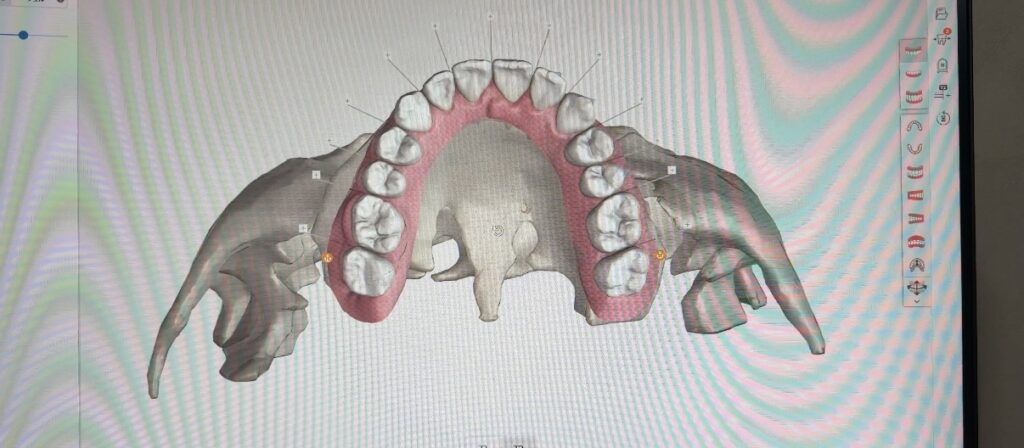

✔️ 精密なデジタルシミュレーションにより、ゴールをイメージしやすい治療